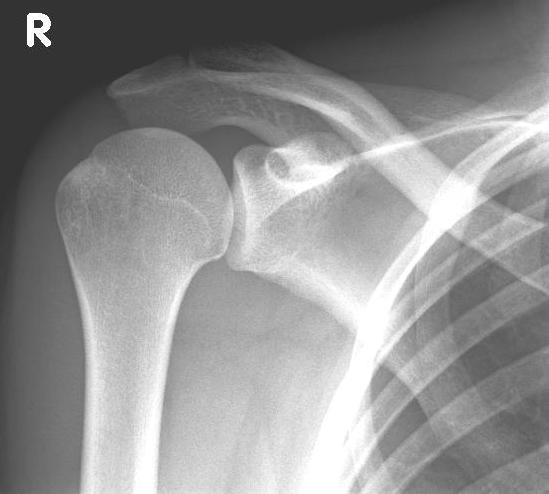

left: X-ray image of an omarthrosis

X-rays can be used to reliably diagnose the extent of joint wear. In the case of severe osteoarthritis, for example, the joint space and the formation of jagged edges (osteophytes) can be detected. If additional damage to the tendons of the shoulder (rotator cuff) is suspected, ultrasound examination (sonography) or magnetic resonance imaging (MRI) can help clarify the situation.